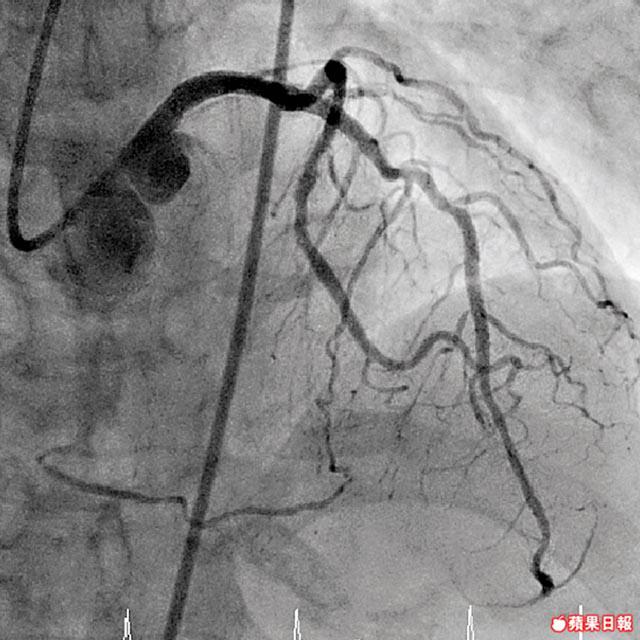

一般頭痛,時間短,最多維持30分鐘,且服食頭痛藥便會見效,但鍾醫生說偏頭痛就麻煩得多,「一頭痛,每次至少要痛4個鐘才會無事,而且食一般頭痛藥不見效,正常處理頭痛的藥物可以分為3個級數,最簡單(一般頭痛)就是用必理痛或NSALD(非類固醇式治療藥),如果是強烈的(偏頭痛),就可以服食令血管收縮的藥物(如Triptan等),見暈就要食止暈止嘔藥物。」如果患有偏頭痛而不肯正視,中西醫均指後果可以很嚴重,譚醫師說,若腦細胞長期缺氧影響循環,會影響視力、大腦判斷分析以及邏輯思考的能力,但都要視乎受影響的神經範圍而定;鍾醫生更指,長時間偏頭痛會增加中風機會,「這個問題是跟血管收縮有關,但真是屬於嚴重個案,不太常見。」